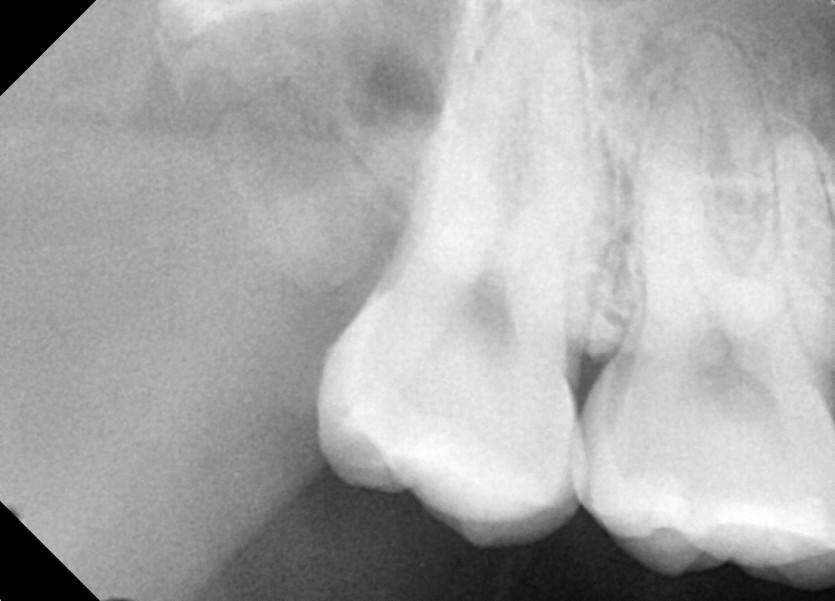

#18,48 사랑니 발치

구강외과 전문의가 당일발치했습니다.